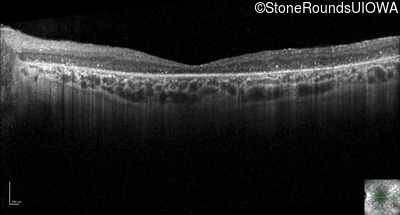

Optical Coherence Tomography - Left - 20/300 sc

Exemplar / OCT Stack